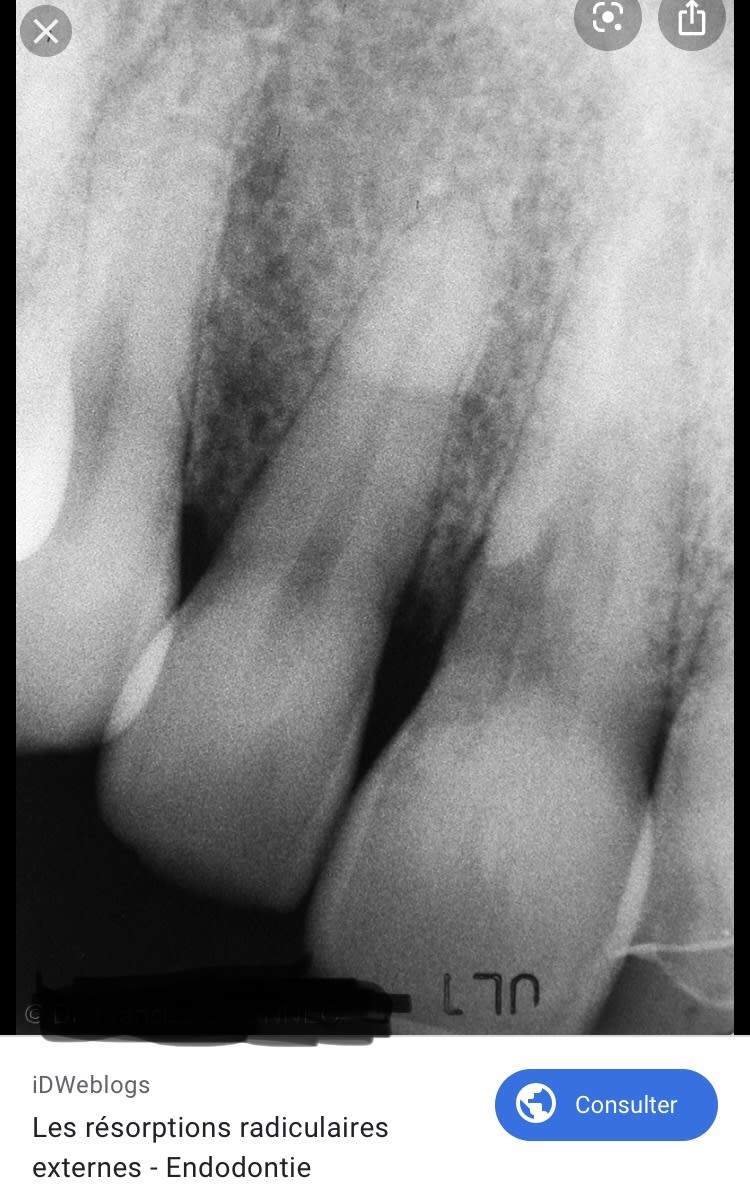

Toute la racine de 27 est bouffée !

La perte osseuse est la conséquence du truc et pas la cause.

On a l’impression d’une rhizalyse périphérique.

Corrosion, fêlure, sur occlusion, scew post...

Résorption interne, elle est en mesial de la pointe du screw-post. On la voit sur les Rx, surtout la retro-alveolaire et elle debouche au niveau de la lesion paro.

C’est une résorption cervicale externe et non interne :) Celle-ci tu l’as pas vu venir :)) on fait moins le malin tout d’un coup :)))

Bin non. Elle debouche pleine poche, tu vois sur la retroalveolaire la perfo qui va de dedans vers dehors.

Tiens regarde résorption cervicale externe :

Ça ressemble à ça non ?:)